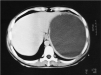

Fig. 1. Lesión quística intraesplénica de contenido homogéneo, con bordes regulares que no infiltran tejidos vecinos, de unos 18 cm de diámetro en su parte mayor, compatible con quiste simple.